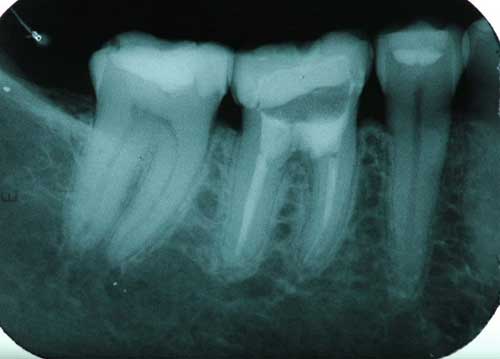

Paciente de raza mestiza, de sexo femenino y 30 años de edad presentó perforación furcal accidental durante el tratamiento endodóntico del diente 36. Después de 2 días este fue referido para nuestro servicio. El paciente no presentó ninguna complicación al examen clínico general, ni antecedentes que puedan alterar el curso del tratamiento. La perforación de la furca fue confirmada con una radiografía del diente, la cual mostró una imagen radiolúcida compatible con la lesión (Figuras 2.1, 2.2). Las opciones de tratamiento fueron discutidas con el paciente y el plano de tratamiento para reparación de perforación radicular con MTA fue sugerido y aceptado por este. El material restaurador provisional fue retirado y la cámara pulpar fue irrigada con solución de hipoclorito de sodio al 1 % para el control de la hemorragia y para poder evidenciar la dimensión de la perforación. Posteriormente el tratamiento efectuado con MTA (Angelus®) fue el mismo al anteriormente descrito. La radiografía final del procedimiento presentó la extrusión del material dentro de los tejidos perirradiculares y sellando el defecto (Figura 2.3). Después de 10 días, el paciente se presentó asintomático. Luego de 6 meses fue realizado el primer control, en el cual fue observado radiográficamente un inicio de formación ósea (Figura 2.4). Después de 1 año fue realizado un segundo control, en el cual la formación ósea se hace evidente (Fotografía 2.5). O resultado y el pronóstico fueron satisfactorios.

Figura 2.4

Control después de 6 meses